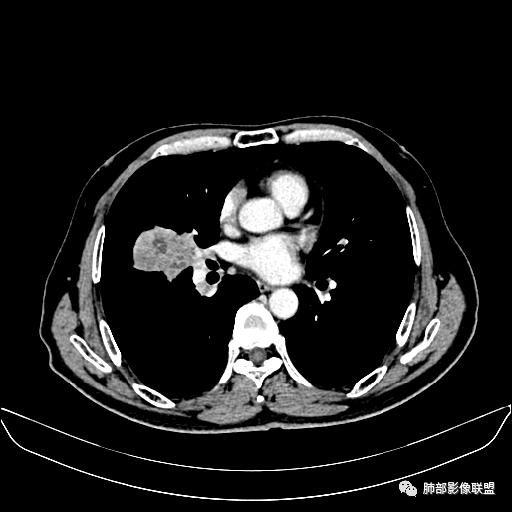

住院4天后行胸部增强CT

静脉期

老年男性,因“咳嗽咳痰1月余。”入院。病程中咳嗽咳痰,咳黄白痰,间断咯少许鲜红色痰血。PPD阳性。胸CT:右肺中叶外侧段支气管管腔阻塞,大片实性病变,病灶边缘光滑,部分边缘膨隆,可见分叶,肺门及纵隔可见肿大淋巴结,并可见钙化。增强可见病灶明显强化,而且延迟强化明显,病灶内多发低密度区,内见血管影,血管变细、部分血管破坏。考虑恶性病变可能性大,鉴别慢性肉芽肿性病变。

胸CT:跨叶大肿块,主体在中叶,右中叶外侧段支气管阻塞,病灶部分边缘膨隆,可见分叶,部分边缘平直,肺门及纵隔可见肿大淋巴结。增强病灶不均匀强化,延迟强化明显,病灶内多发低密度区,内见血管飘浮,部分血管变细、模糊。考虑:恶性病变可能性大,大细胞?淋巴瘤?鉴别慢性肉芽肿性病变。

右肺中叶软组织肿块,外围向内生长,叶间胸膜向前内移位,肿块近肺门侧跨叶,中叶外侧段支气管截断,密度不均匀,双侧肺门及隆突下见肿大淋巴结,增强后呈中度不均质强化,肺动脉供血,多发坏死区,边界尚清,坏死区域内见结构,结合病史考虑恶性,鉴别诊断1结核,爬行征是沿支气管树分布,外宽,内窄,周围有卫星灶,内气管狭窄后扩张,此例沿叶间胸膜长轴分布,气管有截断,不典型。2炎性肉芽肿,符合的地方下方层面增强后延迟性轻度环形强化,不符临床无发热等急性感染病史,实验室指标不符,病灶周围渗出及慢性炎性改变有,不明显。